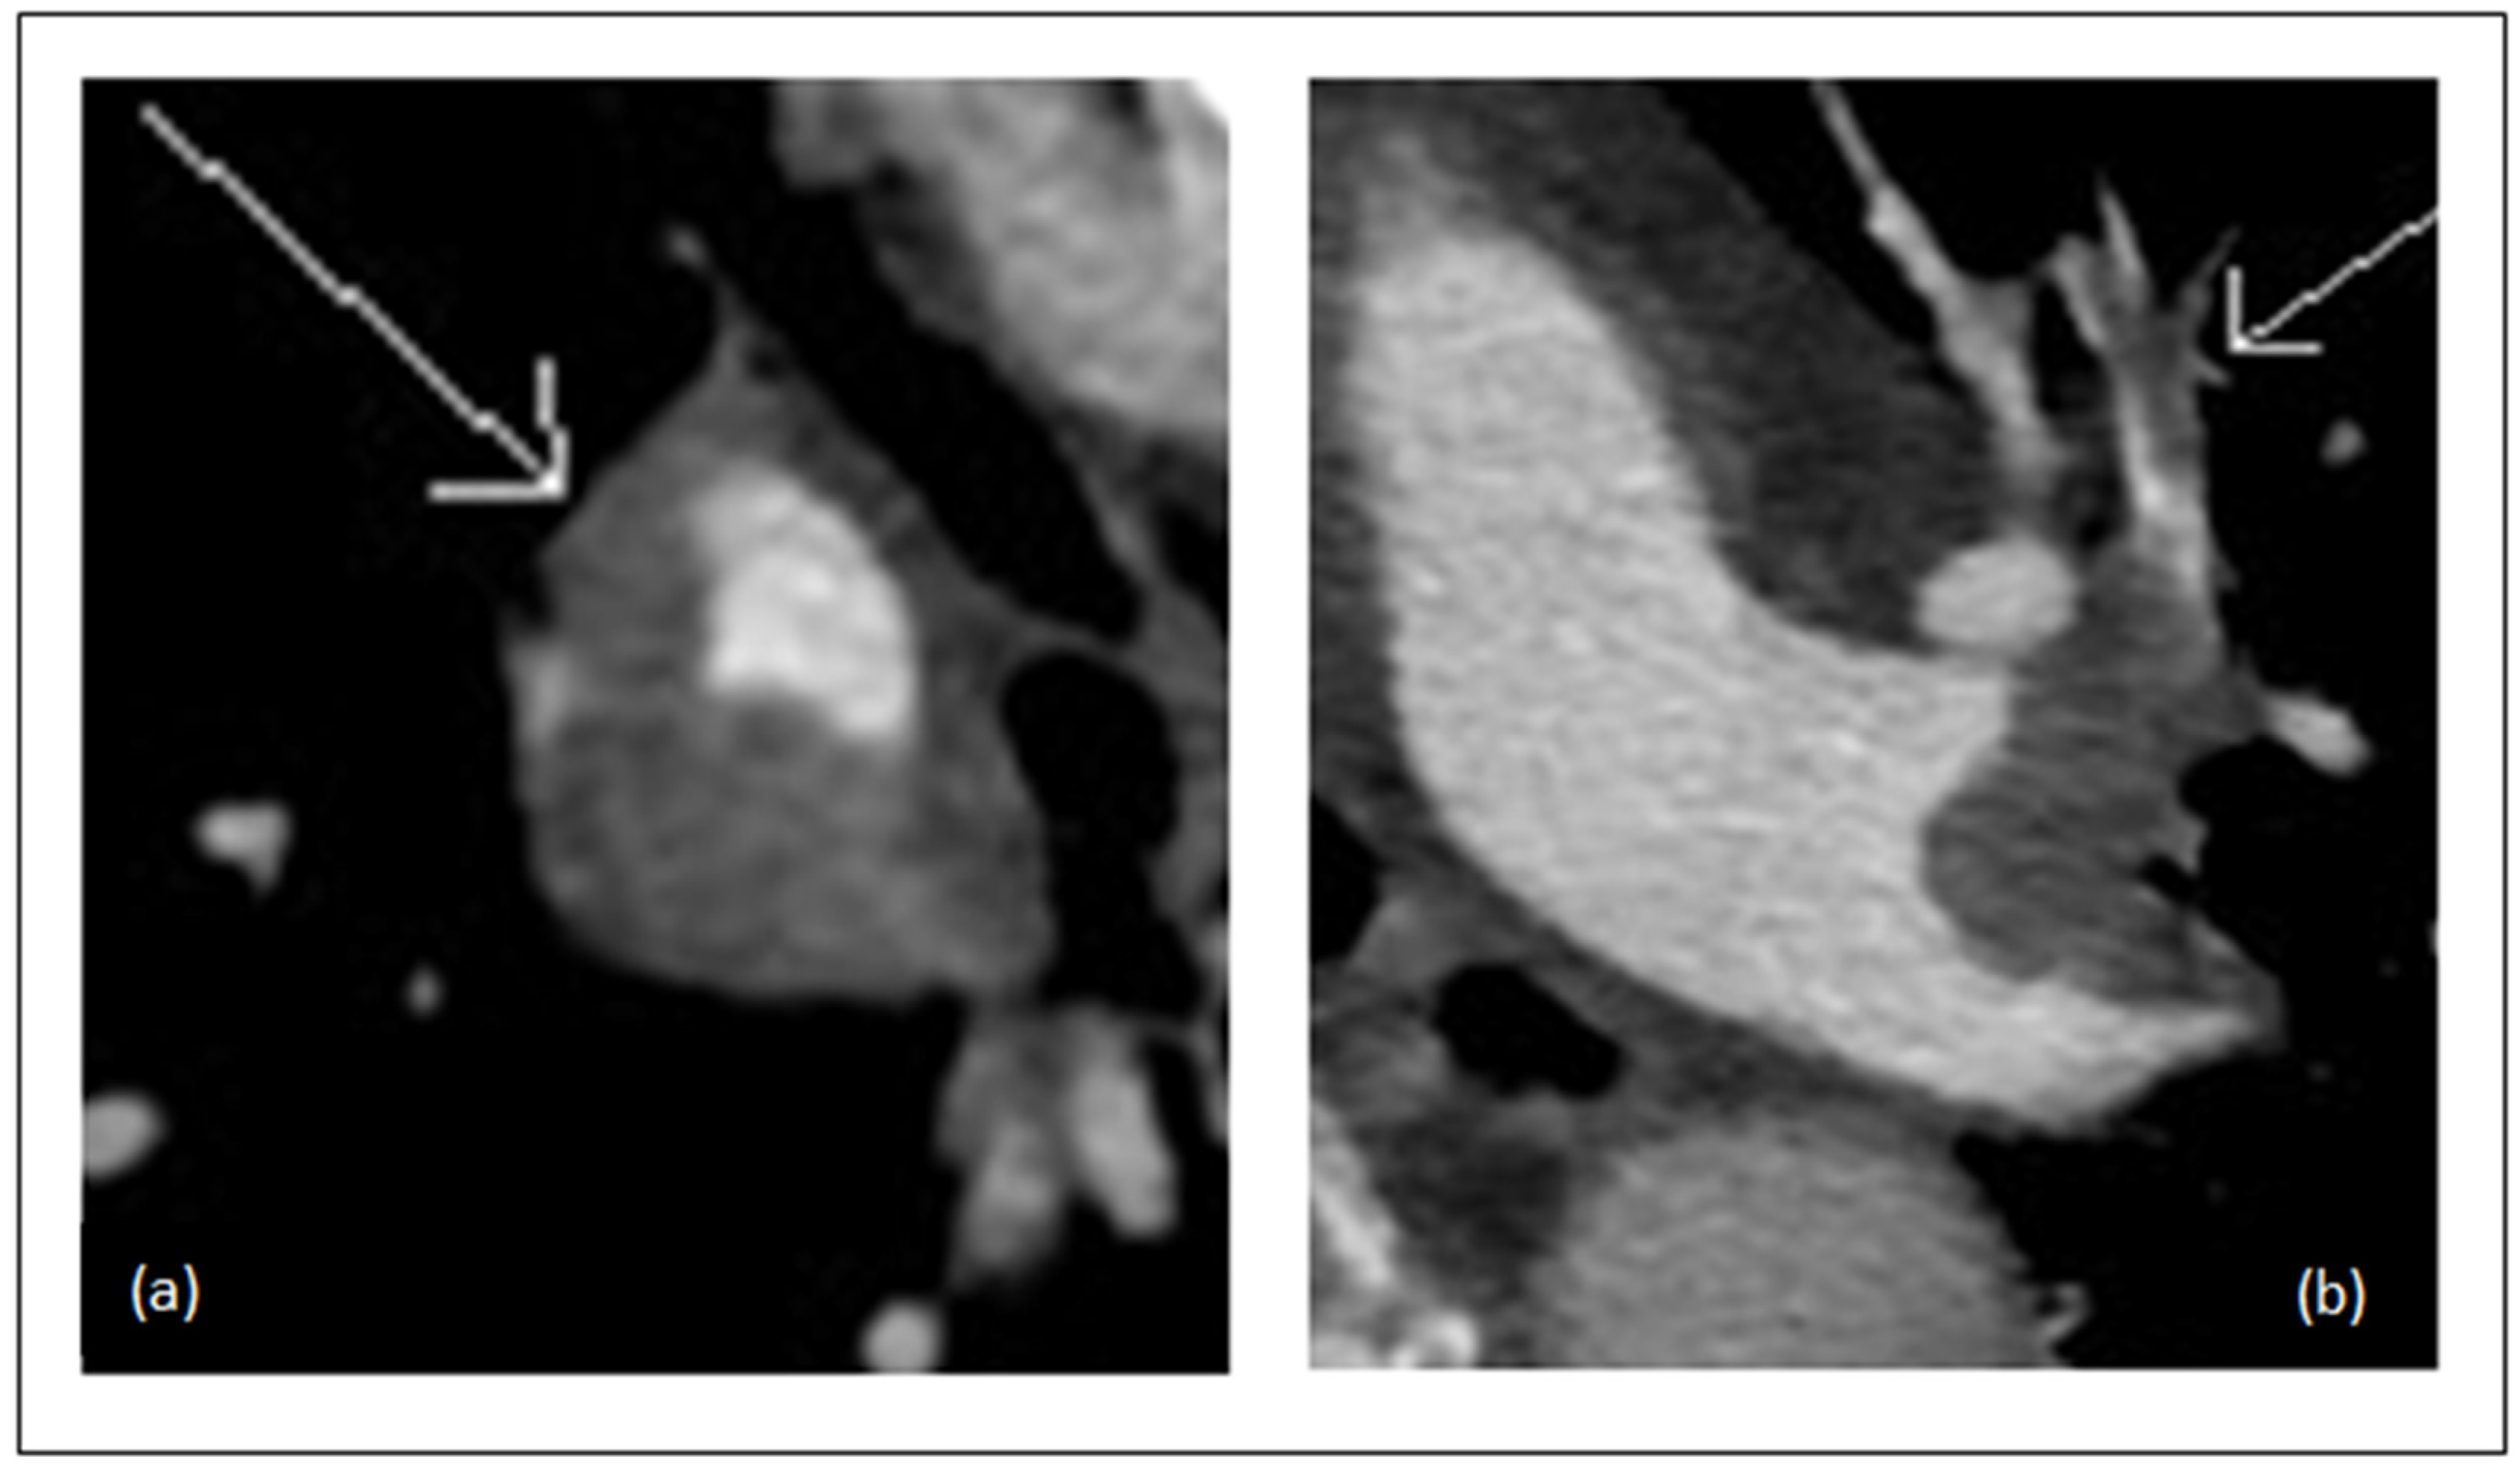

2.5. RVD Assessment